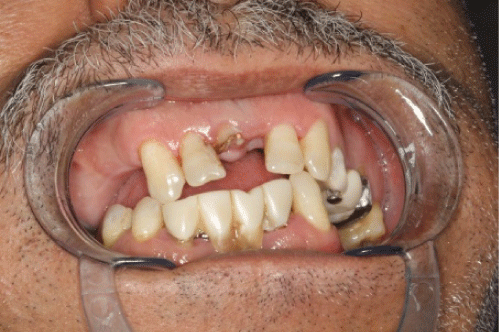

The patient is an 65 year old man without systemic problems with a fractured crown of tooth number 8. The patient stated that he had a motorcycle accident about 3 months ago and he suffered from this fractured tooth due to impaction and severe pain.He had RCT treatment 9 weeks ago,but after the pain subsided, he did not return for further treatment due to his economic problems. He had visited several centers for treatment in the last few days, but he had not achieved any results, and finally, due to deep decay in mesial and distal, he was advised to extract the tooth. When he was clinically examined in Restorative Dentistry Department of Tehran University of Medical Sciences, the RCT treatment was assessed and the decay was entered into the coronally aspect of the root. The deepest carious area was located approximately 2 mm below themesial bone crest, so during crown lengthening surgery, at least 5 mm of bone had to be removed from this area to reach the minimum acceptable amount of healthy tooth tissue, excluding the bone from the mesial side of tooth number 8 (Figure 1). This procedure required extensive osteectomy on adjacent teeth, and performing it on the central teeth of the upper jaw would have created significant cosmetic problems for the patient. Considering the mentioned problems, the patient's age and, the best cost effective choice in this case was forced eruption.

Figure 1: Tooth number 8 at first visit of 65years old patient. View Figure 1